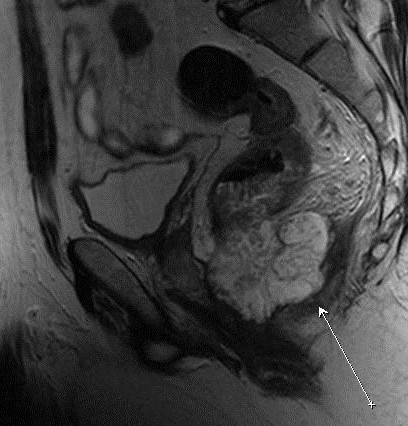

На снимках визуализируются отдаленные участки кишечника, мочевой пузырь с мочеточниками, тазовые кости, у женщин – матка, яичники, влагалище, у мужчин – семенные пузырьки и простата.

Что показывает МРТ малого тазаПри исследовании женских тазовых органов на снимках оценивают состояние матки и яичников, количество фолликулов, спаечные, воспалительные и опухолевые процессы. При проведении МРТ яичников проводится сканирование маточных труб, что имеет большое значение для диагностики оофирита, сальпингита и других воспалительных заболеваний маточных труб и яичников, кистозных образований, агенезии, лишнего яичника и других пороков развития, а также злокачественных процессов.

МРТ оценивает расположение и структуру органов малого таза, оценивает характер их содержимого и видит изменения в структурах менее 1 см, что особенно имеет значение для диагностики эндометриоза.

МРТ органов малого таза что показываетПомимо этого МРТ малого таза показывает камни в мочевом пузыре и мочеточниках, последствия перенесенных травм живота, которые могли сопровождаться разрывом органов, нарушения предстательной железы и прочие процессы.